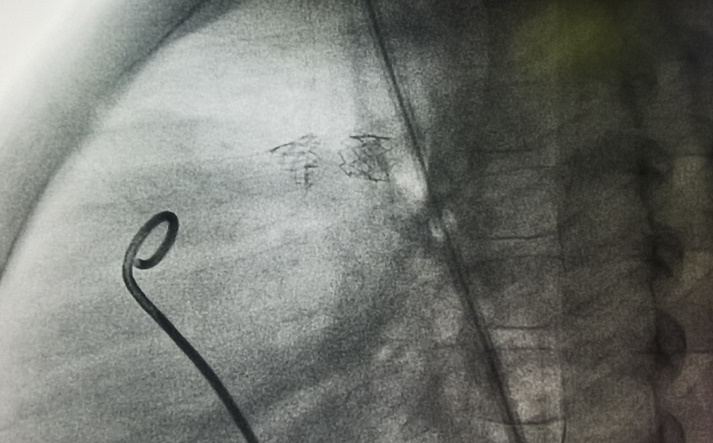

2021年5月18日,支架术后2个月再复诊,CT显示支架形态良好,未发生再次断裂。未来择期再进行Pul-Stent支架再扩张。